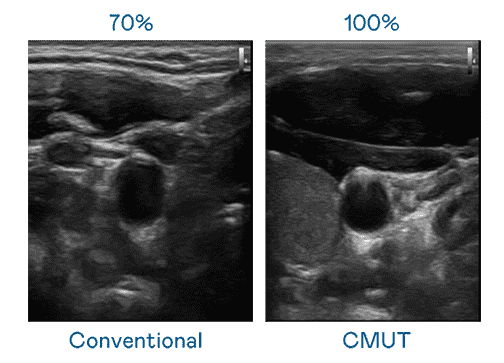

CMUT 技术是一种用电容式微机电元件来产生超音波讯号的技术。。与传统 PZT 压电式技术相比,,,,CMUT 频宽增加 30%,,,更宽频的超音波讯号让影像解析度大幅提升,,是实现高影像品质医疗超音波扫描、、、促进精准医疗发展的关键技术。。

大频宽带来超清晰影像

超音波影像的解析度高低,,,首先取决于探头能发出的讯号频宽。。www.z6.com CMUT 可提供高清晰的超音波讯号,,提供高频宽、、、高灵敏度、、、影像纹理细节更高的超音波影像,,协助医护人员缩短影像判读时间及利用精准的医疗影像进行诊断。。